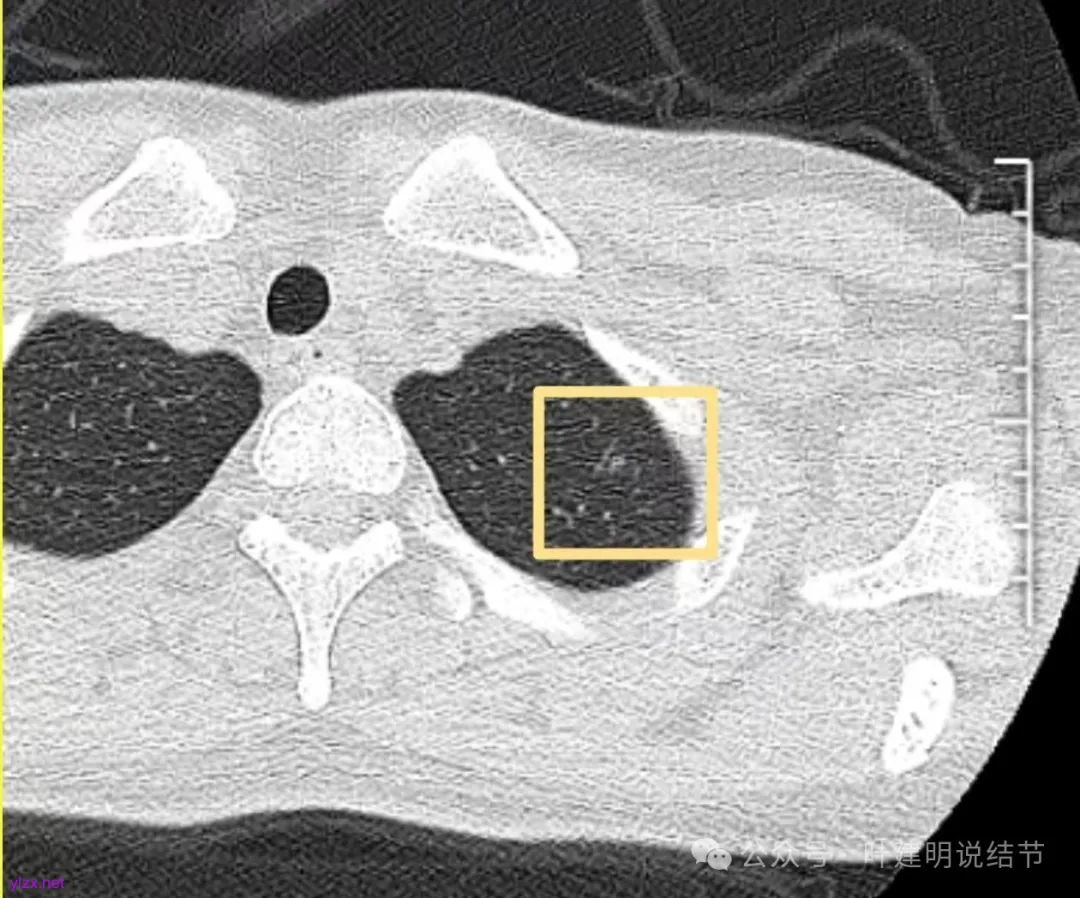

先来看2024年12月的影像:

左上叶淡而轮廓欠清楚的磨玻璃结节,缺乏聚拢性,没有收缩力。

再看2022年9月的影像:

右下当时是很淡的,也显偏模糊的磨玻璃影。

怎么有个点状密度较高的结节在?与上面那截图的淡磨并不完全在一块的。

密度甚高,边界与轮廓清楚,只看这真的不像恶性些。

两肺多发结节,左侧黄色标注的考虑是肺泡上皮增生可能性大;蓝色的考虑肺泡上皮增生或者少许慢性炎可能性大;右侧红色宽起来并带有红色箭头的这处是主病灶,偏混合密度,整体轮廓较为清楚,边缘显得毛糙,从2024年12月份的来看,要考虑是肿瘤范畴,原位癌或者微浸润性腺癌可能性较大,也不能完全排除不典型增生。但是在2022年的时候,这个病灶的边上也有一个实性的微小结节,如果只看2022年的,这么小的实性结节,又比较圆,表面也显得较为光滑,是要考虑良性的,当然太小了需要动态观察。回头再重新来看2024年底的,发现绿色箭头所指的这个微小实性的较2022年几乎没有变,去仔细寻找2022年的,发现当时在实性结节旁边也有密度很淡的一点磨玻璃影(也可能真的就是一处,只是扫描不够薄,密度的变化有些突兀而已),而到了2024年12月份,实性微小这处没有明显变化,但是原来很淡的磨玻璃变成了混合磨玻璃,范围也明显扩大。所以总体来看右肺下叶这处是考虑恶性的,而且从磨玻璃结节角度来讲,还是生长比较快的,就是说还是有一定风险的。加上左侧还有两处也是磨玻璃持续存在,虽然边缘轮廓显模糊一点,但多年以后也可能仍然要变成原位癌或者微浸润性腺癌之类的东西。通盘考虑以后,我倾向于右侧近期单孔胸腔镜下微创局部切除,左侧随访观察,等到有进展并风险增加再来考虑处理。意见供参考!